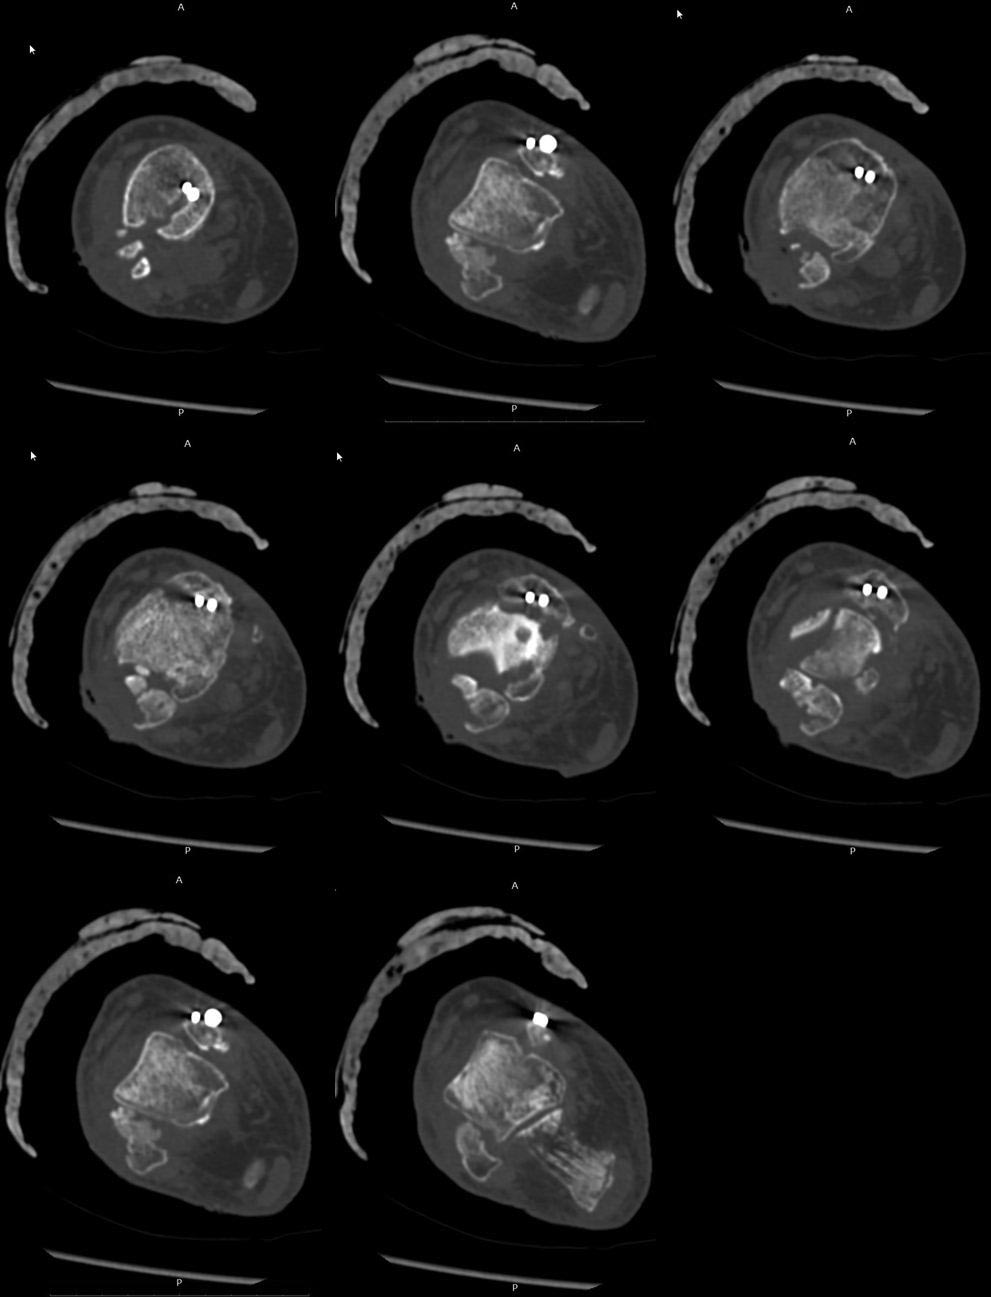

Re: Хронический послеоперационный остеомиелит.

КТ